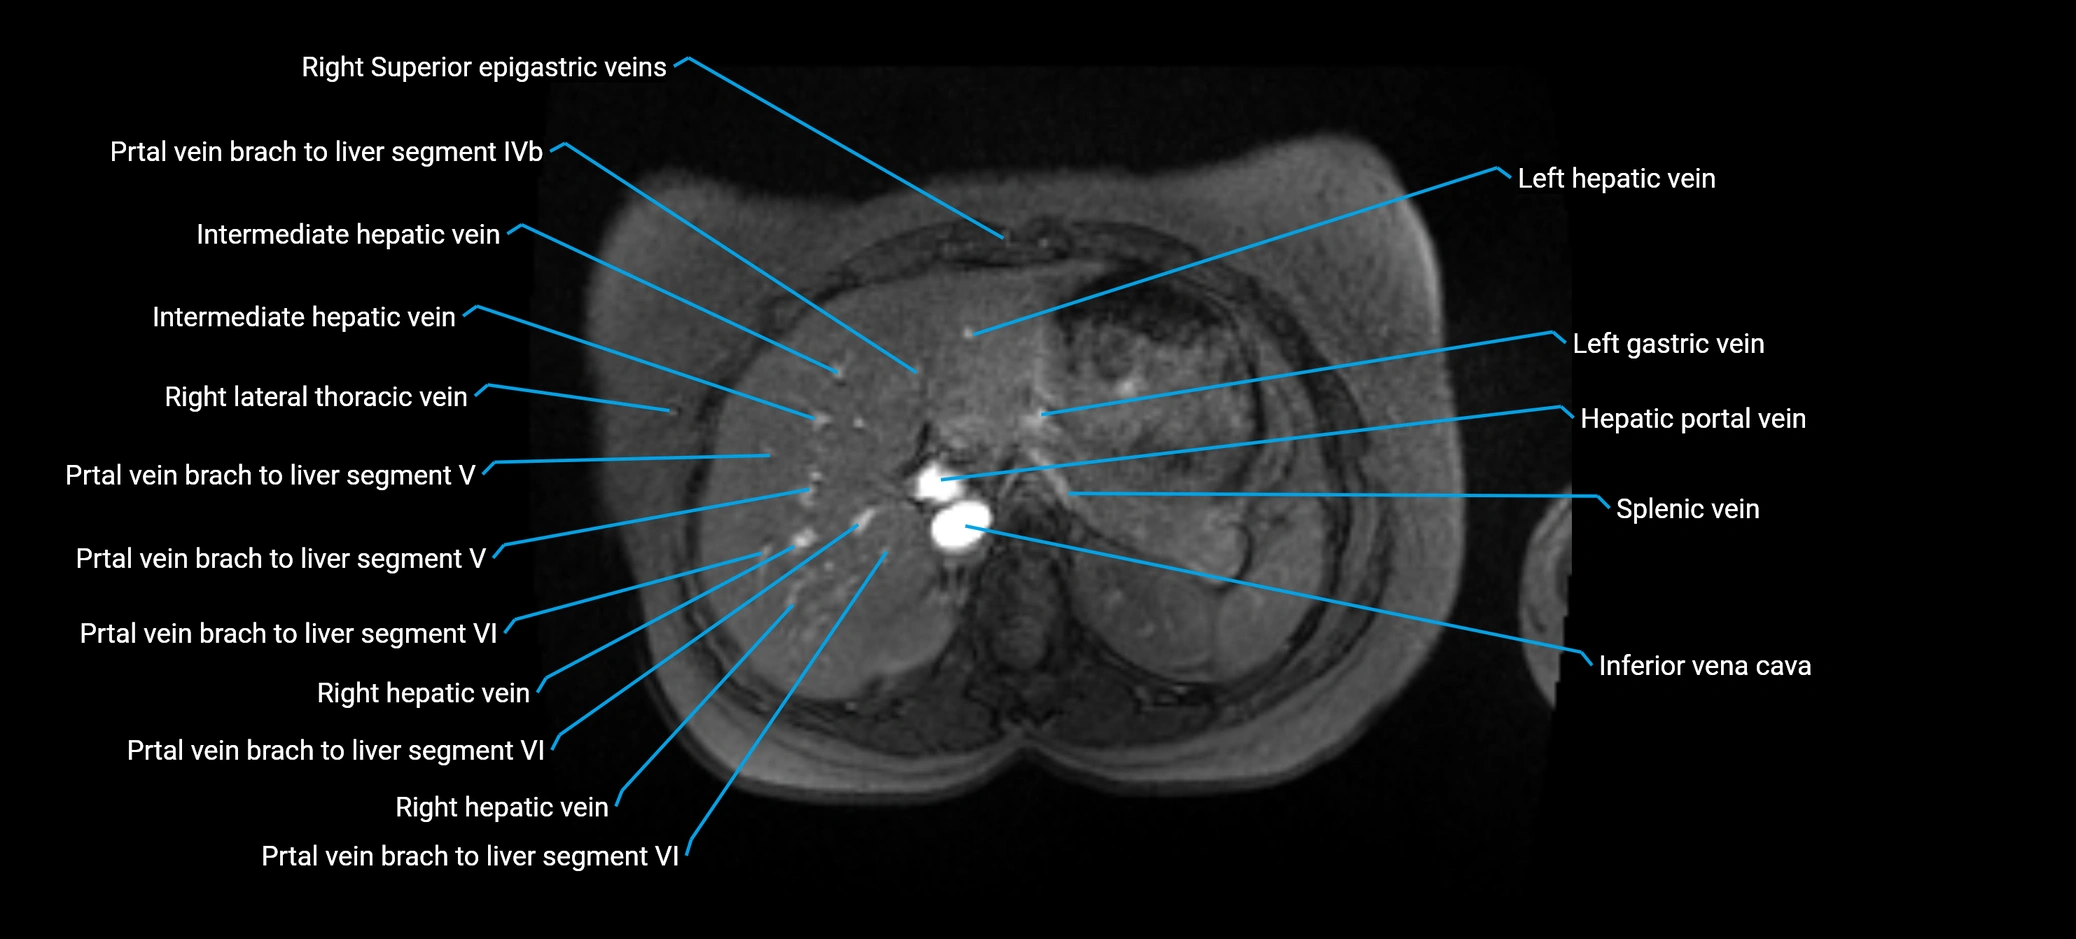

MRV TOF (Time-of-Flight MR Venography):

• Appears as a bright, high-signal vascular channel representing flowing blood

• Clearly shows branching pattern of right portal vein into anterior and posterior branches

• Best in coronal or axial reconstructions for segmental mapping

• No need for contrast, relies on flow-related enhancement

• Clearly delineates branching into segments V and VIII

• Best sequence for evaluating patency, caliber, and anatomic variants